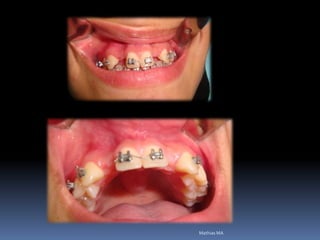

•Necessidades de reabilitações prévias

Dentística, periodontia, cirurgia, prótese, endodontia , ortodontia e DTMs

Reabilitação por implantes abre a visão de um

planejamento prévio, melhorando as condições da

área de trabalho antes da fixação por implantes

•Dentística/prótese

•Endodontia/periodontia

•Cirurgia/ortodontia

•Disfunções articulares